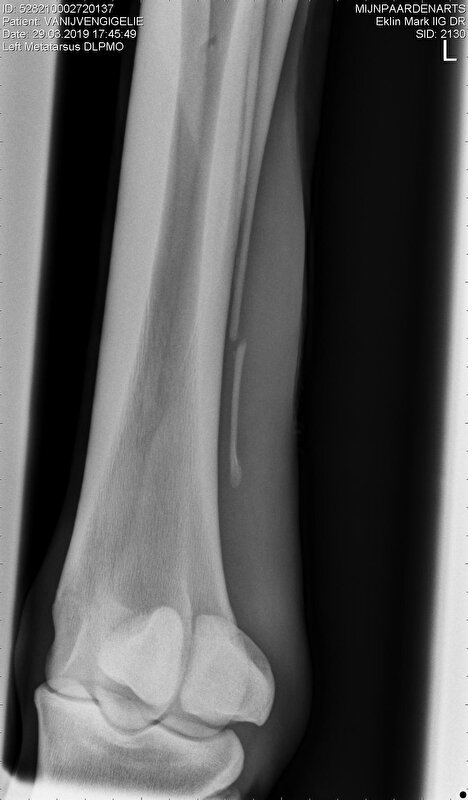

Na 4 weken (in totaal dus 7 weken na wond) opnieuw foto’s gemaakt, blijkt wel wat beweging in te zitten gaven ze aan, geen botwoekering, dus eigenlijk nog week 6 weken bosrust en dan opnieuw foto en evt. scan maken van pees. Het nadeel alleen nu is dat alle paarden ook weer op het land gaan en ze niet rustig in der afgezette graspaddocks blijft staan dus besloten haar opbouwend met de groep mee te laten gaan zo’n 2 uurtjes per dag waarbij ze miss 5 tot 10 minuten in de eentje druk is. Daarnaast wel weer apart met het andere paard.

Hierbij de foto's degene die ik naast elkaar gezet heb is links van 5 maart en rechts van 29 maart.

Links dus 5 mrt en rechts 29 mrt